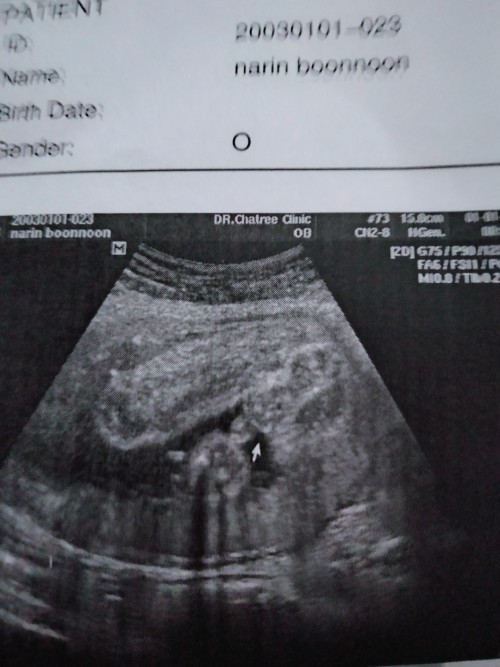

หมอบอกหนูเป็นผู้ชายคับปม

ไม่รู้เพศค่ะ ช่วยดูหน่อย